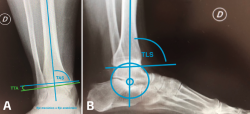

Hay que tener en cuenta que las intervenciones supramaleolares pueden ser suficientes, insuficientes o incluso cambiar una “adecuada” alineación previa del retropié en el proceso de buscar un nuevo equilibrio de las fuerzas de carga. Por esto, siempre hay que tener en consideración la necesidad de procedimientos inframaleolares. Más aún, existen situaciones en las cuales se podría considerar solo una intervención inframaleolar si el caso en particular lo permite. También se pueden identificar presentaciones atípicas de desaxación, aunque menos frecuentes en general, como lo son las deformidades en plano valgo con una interlínea de tobillo en varo. En estas situaciones las actuaciones supra- e inframaleolar serán de sentido inverso (Figura 3).

Figura 3. Malalineaminento en varo tobillo-valgo subtalar (osteotomía –OTT– supramaleolar –SM– de apertura más OTT de calcáneo varizante).

En las radiografías simples con carga se evalúan las deformidades en los planos coronal y sagital. Las mediciones en el plano coronal son la superficie articular tibial distal (TAS-LDTA) con valores normales de 91 a 93° y el ángulo tibiotalar (TTA) con valores normales de 91,5 ± 1,2°. La inclinación talar (talar tilt) se calcula entre la diferencia de la TAS y el TTA. Se considera que un talar tilt con relevancia clínica es aquel mayor de 4°, considerando este valor como límite máximo de normalidad(6,15). La medición en el plano sagital es el ángulo tibial lateral o ángulo tibial anterior distal (TLS-ADTA), con valores normales de 81 ± 5°. En la clasificación de las malalineaciones con OA asimétricas de tobillo se hace más énfasis en la necesidad de corroborar que el centro de rotación del talo (considerado en el centro del proceso lateral del talo) esté en línea con el eje anatómico de la tibia en la radiografía lateral(7,8)(Figura 5).